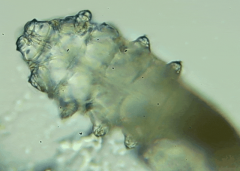

人體上寄生著兩種蠕形螨,分別是毛囊蠕形螨和皮脂蠕形螨,他們通常呈乳白色、半透明的細長狀,擁有四對腳,以睫毛囊上皮細胞、腺體內(nèi)脂質(zhì)為食物,因此主要寄生在面部、眼睛、頭皮等地方,其中寄生在眼睛里的蠕形螨主要活動在睫毛毛囊、睫毛皮脂腺,以及瞼板腺里。

蠕形螨完全長大也只有0.1-0.2毫米,因此肉眼難以看到它們,只有在電子顯微鏡下我們才能看到睫毛根部的一只只蠕形螨。這些螨蟲每天都很活躍,且繁殖速度極快,完成一代生活史僅需大概15天。

螨蟲鏡檢:

在檢查的時候,醫(yī)生要在每個眼瞼上拔出幾根比較典型的睫毛,然后放在光學顯微鏡下,尋找有沒有螨蟲。

如果任意一個眼瞼上發(fā)現(xiàn)了三只及以上的螨蟲,再加上如果你有眼睛的局部癥狀,就需要進行相應的治療了。